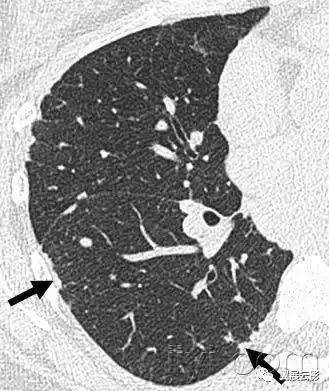

三十九、马赛克征

CT:本征象表现为不同的密度成片状镶嵌,可为间质性病变、闭塞性小气道病变(图)或者血管阻塞性疾病。马赛克征比马赛克样少血或者低灌注具有更强的诊断含义。由于支气管或细支气管阻塞导致的空气滞留可以导致局部的密度减低,在呼气相CT上表现更加明显。

该征象也可以见于间质性肺部疾病,特征是磨玻璃影,此时高密度代表间质性病变,低密度代表正常的肺。